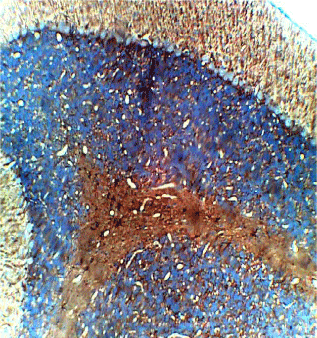

The photomicrograph of the slides obtained from each group is shown in Figures 1 and 2 for H&E and Figures 3 and 4 for GFAP immunohistochemical method. H/E staining showed perturbations in the cerebellum of the group B rats (Figure 2) with shrunken purkinje cells and distorted molecular layer. In general, the cells of the group B (Figure 2) rats were smaller compared to group A (Figure 1). GFAP Immunohistochemical staining also showed high expression of GFAP in the cerebellum of group B (Figure 4) rats compared to group A (Figure 3) rats.

Figure 4. Photomicrograph of the histology of the cerebellum of group B (treated with 4.28mg/kg of lamivudine) showing increased staining in GFAP immunohistochemistry, × 200

Findings from this study have shown that lamivudine had no effects on the weights of the rats (Table 1), but had a degenerative effect on the cells of the cerebellum as shown in figures 2&4 of group B rats compared to figures 1&3 of group A rats and cell count in Figure 5. Our findings corroborated with findings of Ferretti et al. which reported that cerebellar lesions occurred in MRI of patients under lamivudine containing combined anti-retroviral therapy [14]. High expression of GFAP by astrocytes and shrinkage of cells found in the molecular layer suggest cellular inflammation and loss of neuronal fibers. This may render the cerebellar connections ineffective and impair the modulatory function of the cerebellum on other brain centers [22]. This effect may be expressed as depression and dizziness which have been reported as side effects from lamivudine use. This possibility corresponds with the report by Tuner, et al. that cerebellar lesions are associated with reduced pleasant experience in stroke patients [22].